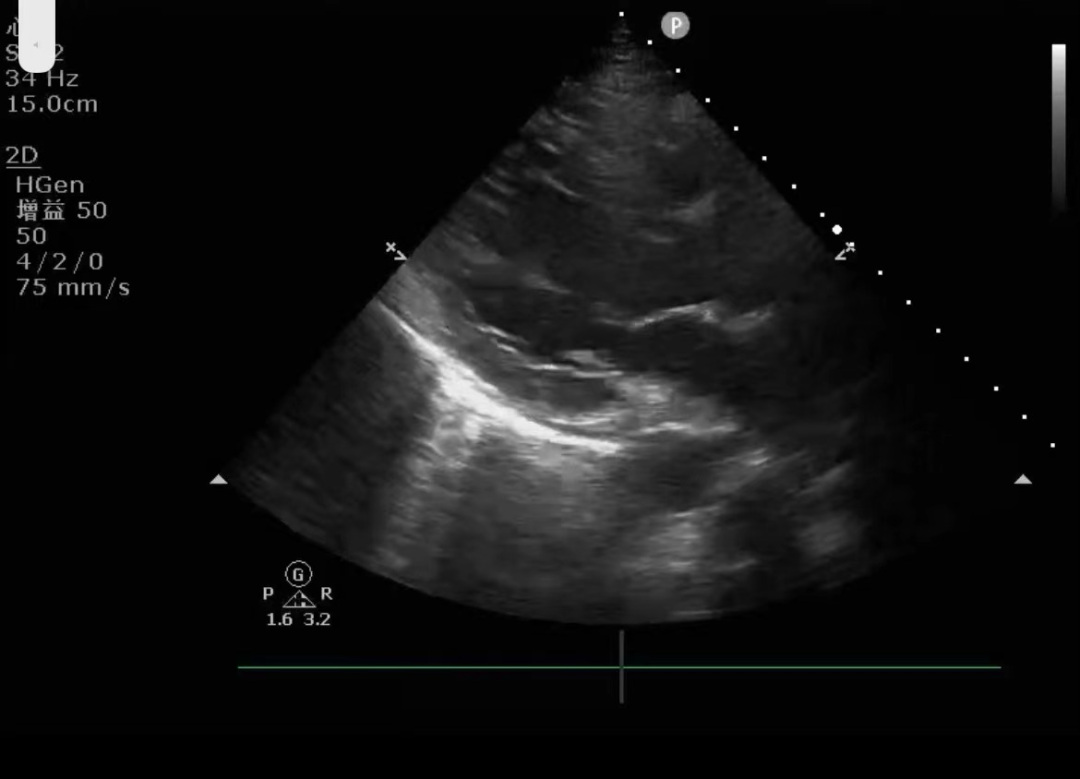

(左室长轴切面)